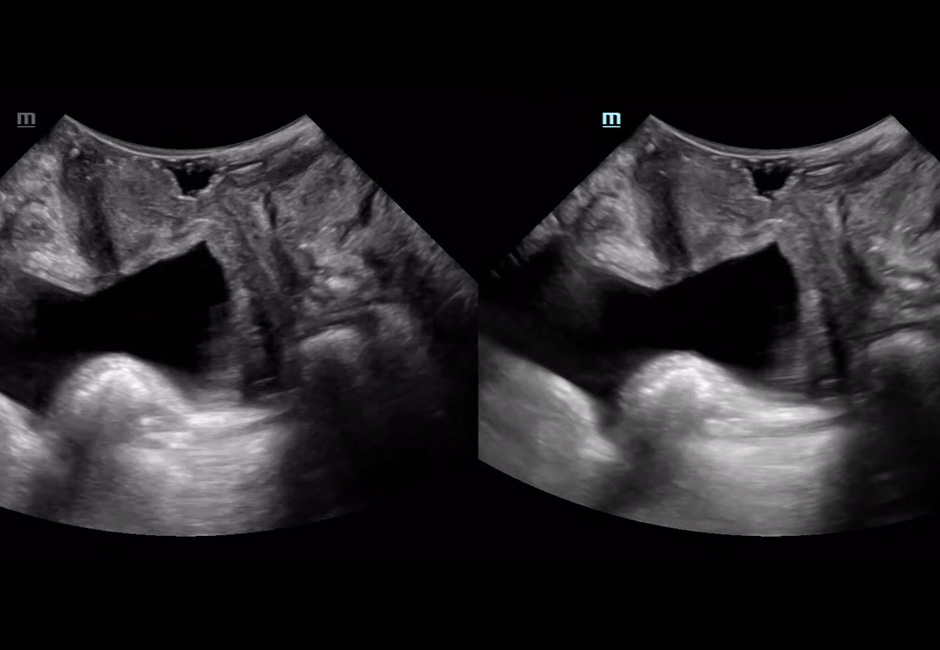

Transverse Section of The Anal Canal

Parasagittal Plane at Contraction